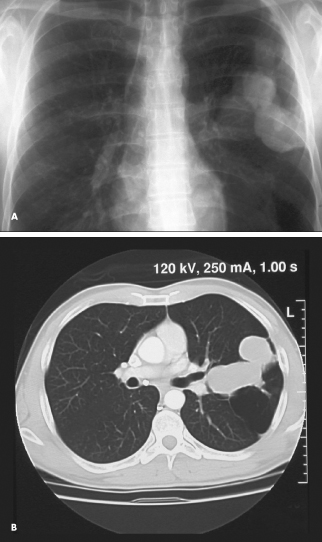

bronchocele

Cheryl Buttram, MD; Kerisea McPherson, MD; L. James Cochrane, MD

<p class="p1"><img src="/sites/default/files/images/1207Con_PCBronchocele_0.jpg" width="90" height="90" style="float: left; margin:...